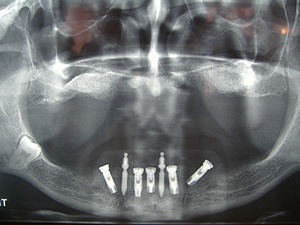

L'examen radiologique panoramique révèle une résorption osseuse importante au niveau des deux maxillaires.

Radiographie panoramique de départ. On peut déjà visualiser l'importante de la perte osseuse aux 2 maxillaires

Nous décidons de placer 5 implants entre les 2 trou mentonniers

Les 2 implants distaux sont volontairement inclinés afin que l'emergeance des implants soit la plus distale possible, nous gagnerons ainsi une dent sur le nombre de dents en extension. (Paolo Malo)